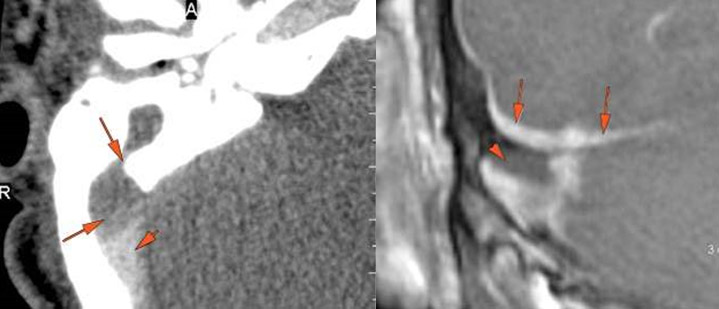

There are dural reactive changes or a subperiosteal/epidural abscess along the sigmoid plate of the mastoid displacing the adjacent sigmoid sinus. [Yes/No]

There is evidence of thrombosis, thrombophlebitis or other occlusive or inflammatory process of the sigmoid sinus, transverse sinus, the vein of Labbe’ or jugular bulb. [Yes/No]

There is evidence of thrombosis, thrombophlebitis or other occlusive or inflammatory process of jugular vein. [Yes/No]

There is a subperiosteal, subdural or epidural abscess along the floor of the middle cranial fossa or along the inner surfaces of the petrous portion of the temporal bone. [Yes/No]

There is brain edema and/or evolving abscess present or, specifically, involving the inferior temporal lobe or adjacent cerebellum. [Yes/No]